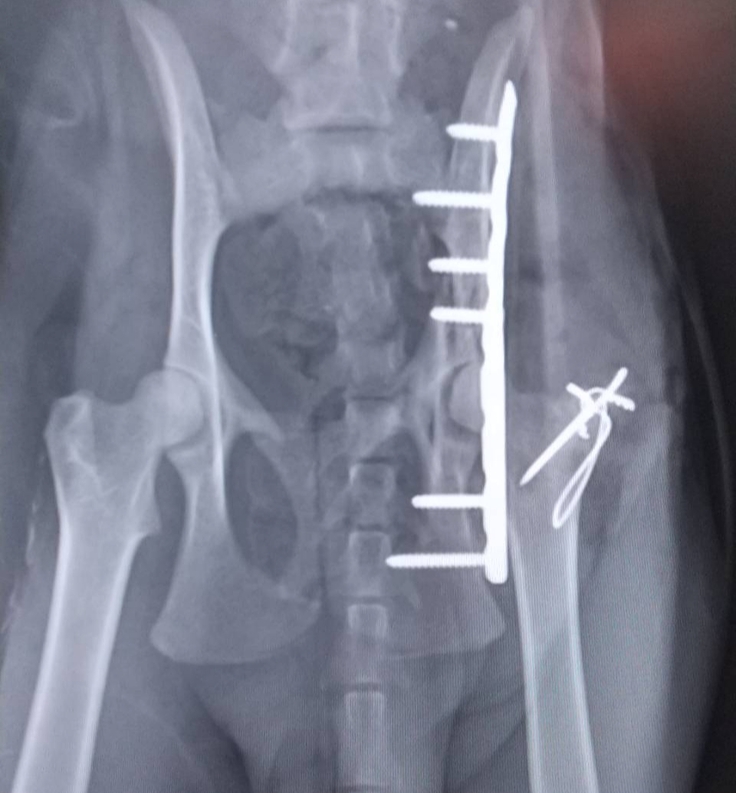

三毛猫ちゃんのレントゲンです

↑手術直後

↑現在

完治告知をいただきました😣✨